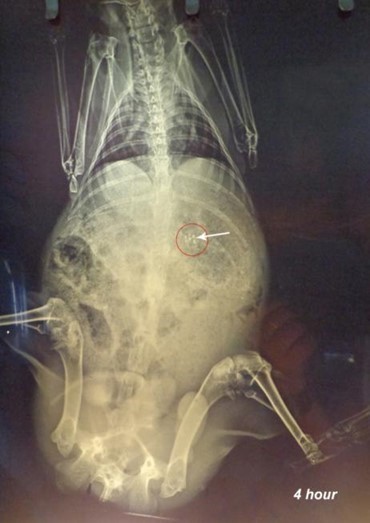

X-ray studies revealed that the microspheres remained in the stomach for the first 2h as shown in fig. (7). Microspheres get released from the capsule shell by dissolving the gelatin shell and distributed in the small intestine as observed in the fig. (8).

Since the particles are small, and the amount of radio-opaque material is also less, the amount of microspheres visible by X-rays is also minimal. Microspheres are visible at 4th h in the small intestine as observed in fig.(8), and some are also seen in the X-ray image taken at the 8th h in the large intestinal region [22]. X-ray image at 10th h indicates the presence of microspheres in the colonic region as seen in fig.(10). The observations were confirmed by a veterinary surgeon. It can be concluded that the formulation is able to target colonic region effectively.

Fig. 8: X-ray image after 4 h